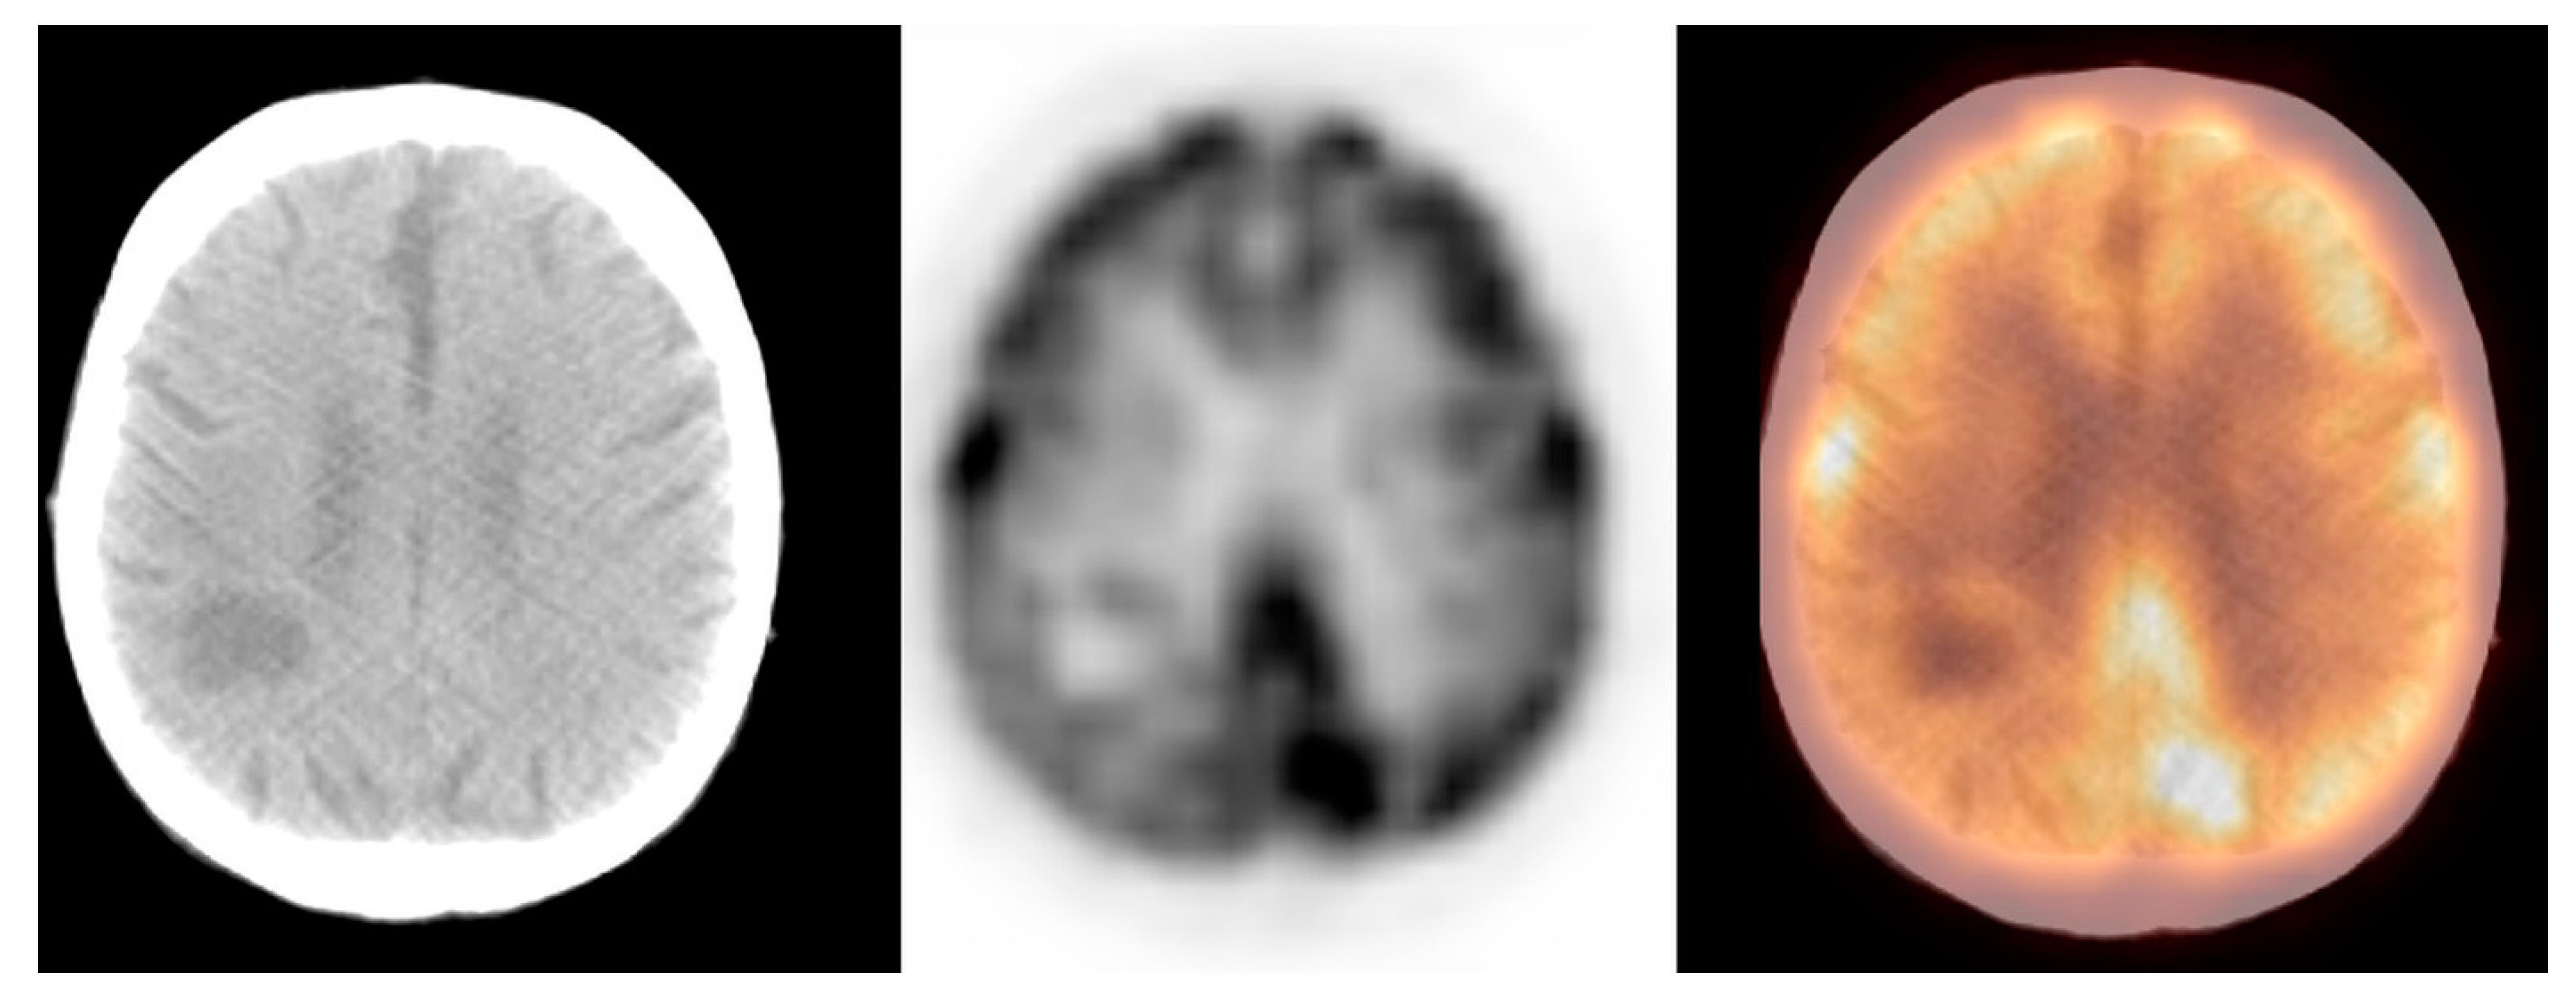

3.2.3. Primary Brain Tumours

| Primary brain tumours | 9.2 ± 4.7 | 9.0 | 1.2–25.0 | [7.3; 11.0] |